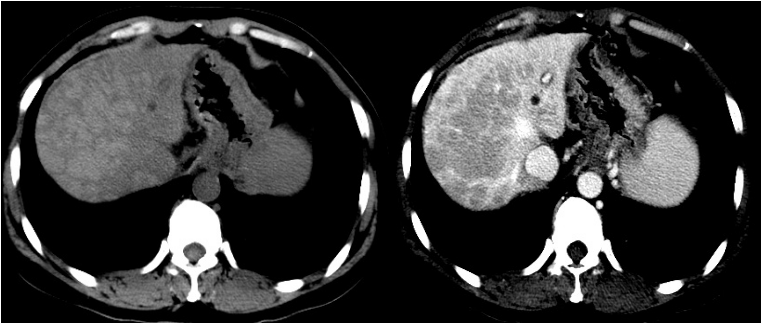

肝肾功能:ALT 223.6 U/L,AST 348.3 U/L,TBIL 338.9umol/L,DBIL 294.7umol/L,Cr 109.9umol/L,ALB 31.7g/L。凝血功能:PTA 30%,APTT 45.5S,D-Dimer 844ug/L。血氨:30mmol/L。血淀粉酶:387.8U/L,尿淀粉酶 294.1U/L。电解质:K+ 2.64mmol/L,NA+ 141.4mmol/L,Ca 2.22 mmol/L。乳酸:2.03mmol/L。心肌酶正常、BNP正常血常规:WBC 5.54×109,PLT 123×109,HGB 114g/L,NEU% 65.8%,CRP 4mg/L,PCT 0.61 ng/ml,G试验129.6pg/ml,GM试验阴性,TB-SPOT 阴性。甲、乙、丙、丁、戊型肝炎病毒标志物检测均阴性,自身抗体:ANA 1:320 胞浆颗粒、核颗粒;其他相关抗体均阴性,特种蛋白示IgG 28.5g/L,IgA 6.05g/L,IgM 3.51g/L,补体C3/C4下降。IgG亚类测定四项均正常。血培养阴性。铜蓝蛋白、24小时尿铜均正常甲状腺功能:TT3、TT4、TSH均下降。肿瘤标记物:AFP 40ng/ml;CA199 372.9U/ml,其他正常。心电图:正常心电图。胸片未见异常超声心动未见明显异常。腹部增强CT(2018-9-28,图1)示1、肝脏炎性改变可能 2、肝硬化不除外,脾大,侧枝循环形成 3、肝囊肿 4、胆囊炎 5、腹膜后及腹腔多发轻度肿大淋巴结,炎性反应性增生可能。

图1 腹部增强CT

病例分析

本文患者为青年女性,无肝病基础,此次发病前因失眠症间断口服中药治疗8月,结合患者临床表现、化验检查结果,考虑诊断“亚急性肝衰竭”。入院前,患者病程已持续2月,入院时合并胰腺损伤、腹腔感染、肾功能不全,经内科综合治疗联合人工肝治疗后,患者胰腺炎、腹腔感染、肾功能情况均好转,未并发其他并发症;但内科治疗维持1月余后,患者凝血功能未见改善,PTA持续在20%以下,反复出现低血糖表现,患者腹部CT提示平扫肝实质密度不均,多发不规则低密度灶,增强扫描肝实质强化欠均匀,可见多发片状强化减低区,同时胃底静脉可见迂曲扩张,脾大,侧枝循环形成;考虑患者肝硬化不除外;另外,值得注意的是,本文患者住院起反复出现低血糖症状,需持续高糖泵入维持血糖水平;在肝功能衰竭时,肝细胞大块坏死严重地影响了肝脏糖代谢。肝脏是糖代谢的重要器官,糖原的合成和分解、糖酵解、糖异生和糖类的转化等维持血糖稳定的代谢活动都在肝脏进行。由于肝脏巨大的储备功能,超过80%以上肝细胞坏死时才会出现肝功能衰竭和糖代谢异常,其中70%以上表现为低血糖;低血糖提示肝脏功能有严重损伤,对于肝衰竭的进展及预后有一定的预测作用。本文患者持续低血糖,侧面反映患者肝脏坏死程度严重,提示预后差,积极控制低血糖有望降低肝衰竭的病死率。